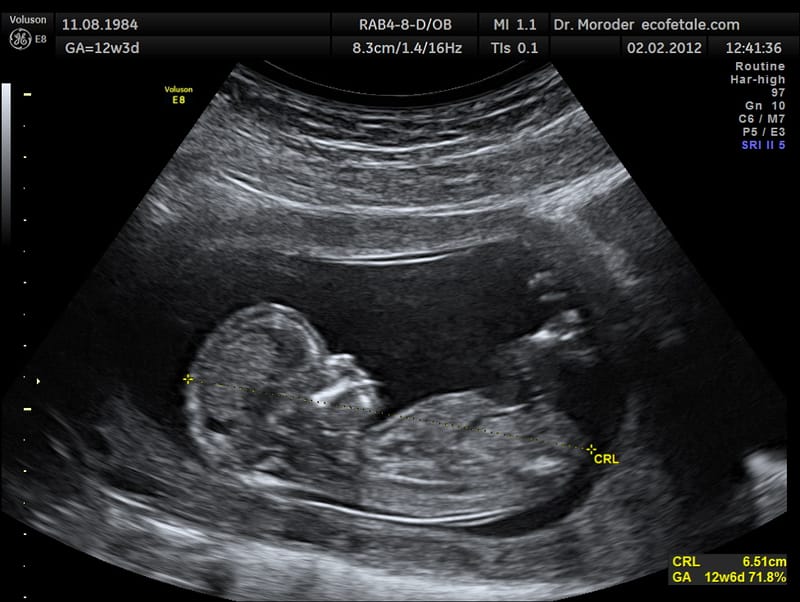

Ultrasound guided procedure as pleural tap. Ascitic tap and biopsy of superficial masses.